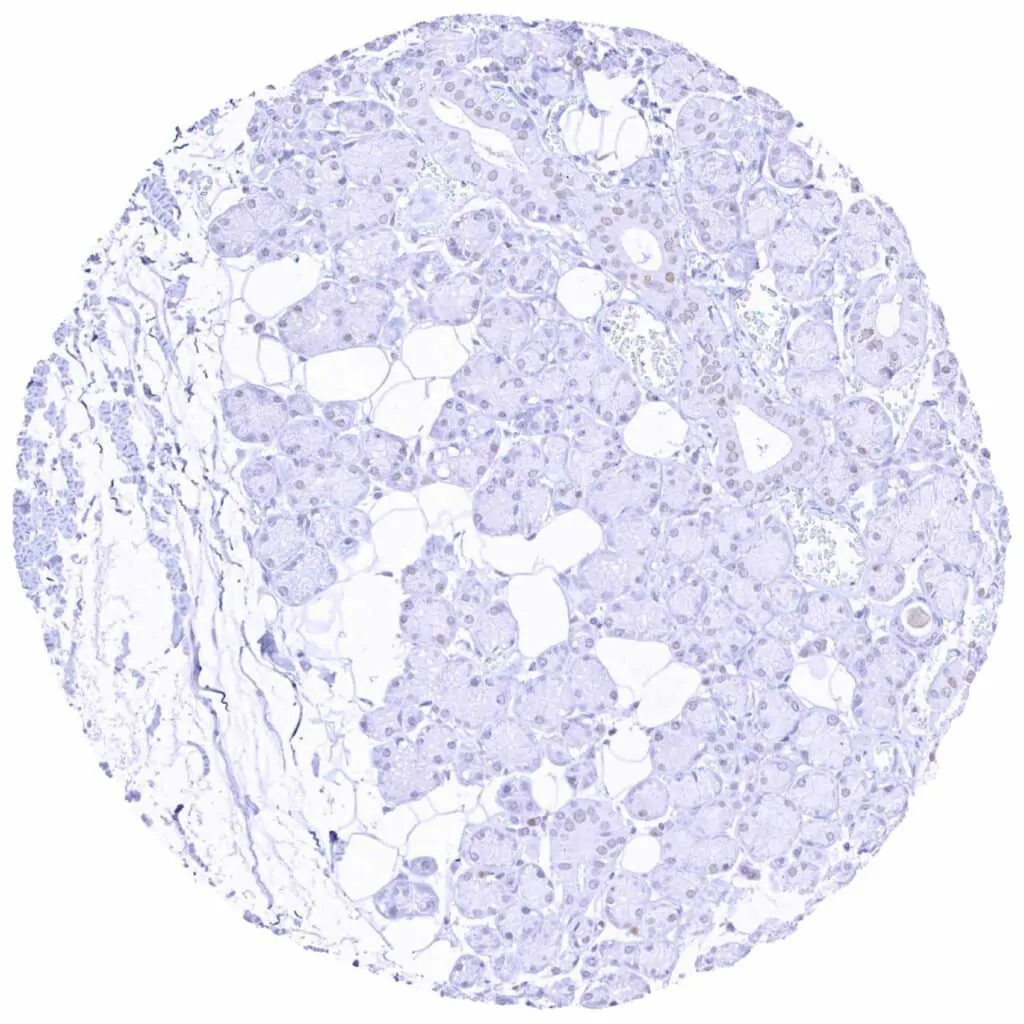

Pancreas